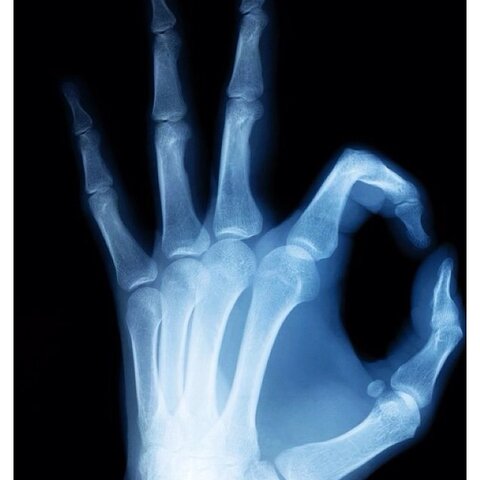

• Primer examen de rayos X en los EE.UU.

Primer examen de rayos X en los EE.UU.

Roentgen publicó la primera imagen médica de rayos X, una imagen de la mano de su esposa. En Febrero de ese mismo año realizó el primer examen de rayos X en el laboratorio de Dartmouth College en Estados Unidos.